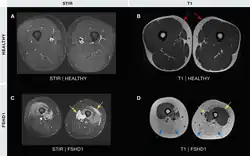

- Magnetic resonance imaging (MRI) is sensitive for detecting muscle damage, even in mild cases. T1-weighted MRI imaging can visualize fatty infiltration of muscles, and T2-weighted MRI imaging can visualize muscle edema. MRI can help differentiate FSHD from other muscle diseases based on the pattern of muscles involved, directing genetic testing.[37][38]

Medical imaging (CT and MRI) have shown muscle involvement not readily apparent otherwise[37]

- A single MRI study shows the teres major muscle to be commonly affected.[38]

- The semimembranosus muscle, part of the hamstrings, is commonly affected,[25][84][85] deemed by one author to be "the most frequently and severely affected muscle."[2]

- Of the quadriceps muscles, the rectus femoris is preferentially affected[84]

- Of the gastrocnemius, the medial section is preferentially affected;[84][85]

- The iliopsoas, a hip flexor muscle, is very often spared.[85][2]